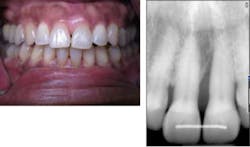

Case No. 2 — Miss Novice

A 12-year-old African American female presented for treatment of localized rapidly progressive periodontitis on No. 19 and No. 30 prior to orthodontic treatment. Prior dental care included prophys and sealants. The LANAP protocol was performed at one appointment with local anesthetic.

Miss Novice before the LANAP protocol.